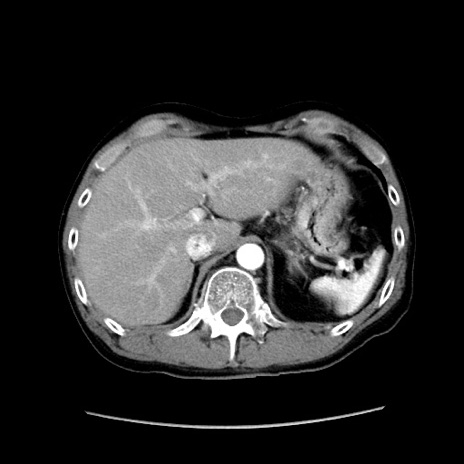

症例37(横断像)

【症例】40歳代 男性

【主訴】腹痛

【現病歴】4時間ほど前に電車に乗車中に臍部上より腹痛出現。徐々に増悪し起立困難となり、救急外来受診。生ものは数日食べていない。今朝お雑煮を食べた。

【身体所見】BT 36.8℃、BP 117/84mmHg、HR 91/min、SpO2 97%、苦悶様、腹部:臍上部広範囲圧痛あり、反跳痛±

【データ】WBC 8100、CRP 0.03